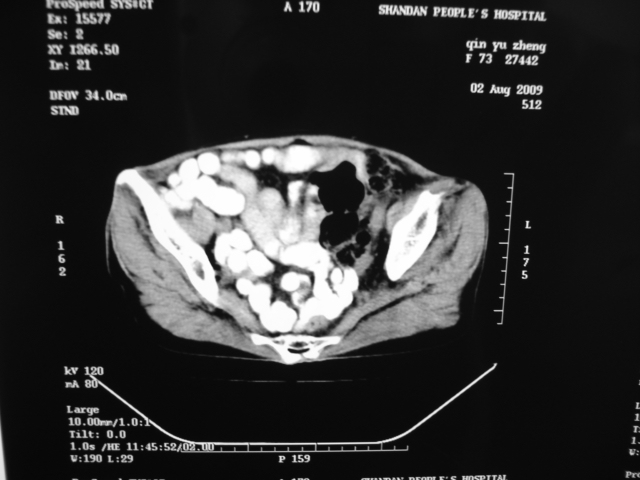

同事奶奶,73岁,腹痛一年,夜晚较重,潜血+++,拒绝增强,考虑左肾ca并腹膜后转移;请各位老师帮忙看看,谢谢!

左肾癌侵及输尿管上段,腹膜后多发淋巴结转移,脾脏钙化灶。至于潜血+++,要考虑消化道病变,本次ct片肠腔未见明显异常。

潜血+++是尿还是便?如果是便,则考虑肾癌侵犯降结肠可能。

1)考虑左肾癌侵犯肾盂并腹膜后淋巴结转移。2)脾脏钙化灶。

查查一胸部,不除外肺癌伴左侧肾上腺,腹膜后淋巴结及左肾转移.

定位像见上肺野也很糟糕,支持7楼。